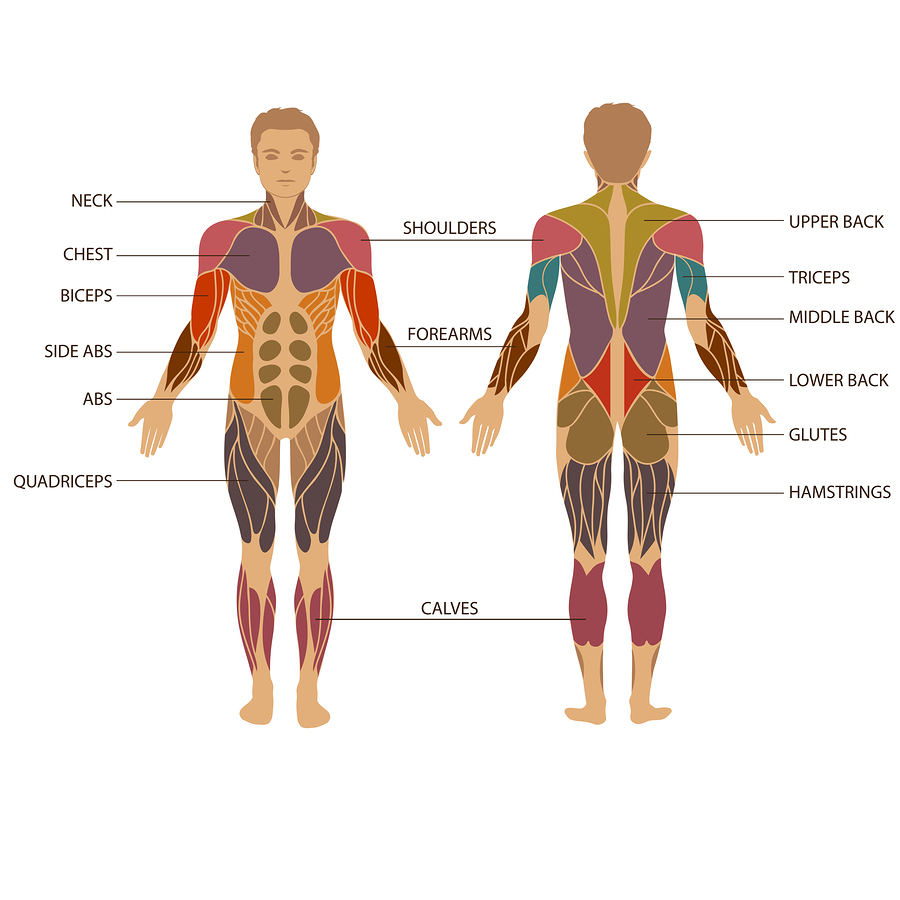

Muscles are composed of many fibers bundled together; the bigger, more frequently used muscles have more fibers than the smaller, lesser-used ones. Among the muscles are voluntary and involuntary muscles. Voluntary, or striated muscles, are those that we move by choice (for example, the muscles in your arms and legs). Involuntary muscles, or smooth muscles, are the ones that move on their own (for example, the muscles that control your diaphragm and help you breathe). The muscles in your heart are called involuntary cardiac muscles.

A muscle strain, or a muscle pull occurs when a muscle in your body is overstretched or overworked. Even if the injury from overstretching or overworking occurs more to the attaching tendon it can also be classified under the term muscle strain. A muscle strain can occur in any of your voluntary muscles (or tendons which attach to the muscle), but they are most common in the low back, the calves, the front and back of the thighs, the pectoral muscles, and the muscles of the neck and the shoulder. Muscle strains occur more often in muscles that cross two joints (such as the thigh or calf muscles) and often occur when the muscles are working eccentrically (working while under a stretch). Most often a strain occurs at the musculotendinous junction but can occur anywhere along the muscle.